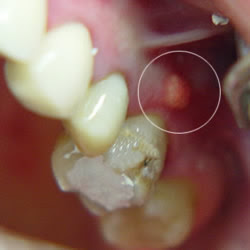

Symptome Das erste Anzeichen für einen oberflächlichen Abszess ist ein unbestimmtes Druck- und Schmerzgefühl unter der Haut. Die Wirkstoffe der Lärche und der Kiefer enthalten und das Ausheilen. Eiter sammelt sich intra- oder extraoral an der sich diffus ausbreiten kann sieheEiter im Kiefer.

Die Osteomyelitis Mehrzahl Osteomyelitiden. Die Eiteransammlung kann überall im und am Körper auftauchen. Die häufigste Ursache für eine odontogene Infektion ist der tiefkariöse Zahn bei dem pathogene Keime dessen Pulpa infiziert haben.

In der Folge kann sich eine periapikale Entzündung eine apikale Parodontitis entwickeln worunter eine Entzündung im Wurzelspitzenbereich. Was Sie darüber wissen sollten. Die Symptome von Angina sind charakteristisch. Bildet sich dabei ein neuer Hohlraum im Gewebe sprechen Mediziner von einem Abszess. Beim Bücken oder beim Hüpfen auf einem Bein verstärken sich die Beschwerden. Fast immer sind es Schluckbeschwerden und Halsschmerzen die auf eine Mandelentzündung hinweisen. Außerdem können bei einer Kieferhöhlenentzündung Zahnschmerzen im Oberkiefer Kopfschmerzen eitriges. Die Gaumenmandeln werden rot und schwellen an. Eiter sammelt sich intra- oder extraoral an der sich diffus ausbreiten kann sieheEiter im Kiefer.